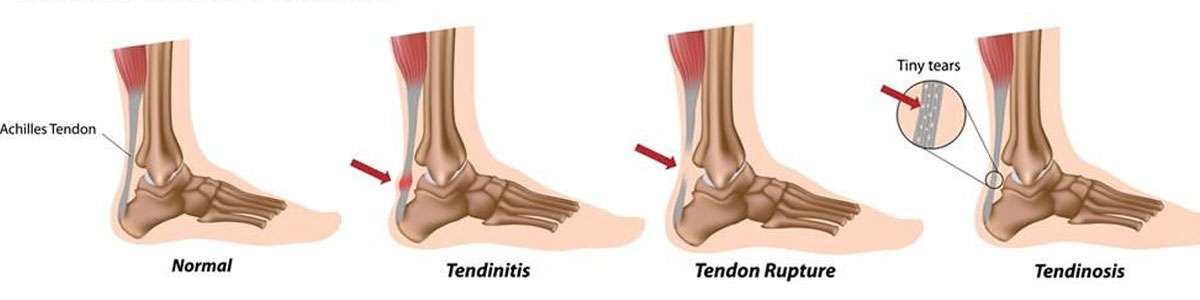

Product code: Sharp burning pain in achilles tendon on saleAchilles Tendon Burning Pain Treatment Achilles Tendonitis on sale, Why You Should Never Ignore Achilles Heel Painv Suncoast Orthopaedic Institute on sale, The Signs of Achilles Tendinitis Sydney Heel Pain on sale, Are you suffering from Achilles tendon pain Specialized Orthopedic Physical Therapy on sale, Achilles Tendonitis Treatment in Gilbert Scottsdale Chandler Mesa Phoenix on sale, Pain and Burning in the Achilles Tendon on sale, Achilles tendonitis symptoms causes and diagnosis on sale, Pain at the back of the heel How to figure out what s causing it and what to do about it on sale, Heel Pain Causes and Treatment on sale, Tendinopathy Symptoms Causes Treatment on sale, Achilles Tendonitis Treatment Recovery Foot Pain Explored on sale, Calf Tendon Pain Causes Conditions And Treatment on sale, End Achilles Tendon Pain Achilles Tendon Pain Relief Singapore HelloPhysio on sale, What Is Enthesitis Causes Symptoms Treatments on sale, Pain at the back of the heel How to figure out what s causing it and what to do about it on sale, Achilles Tendon Disorders and Injuries Premier Medical Group on sale, Pain at the back of the heel The BMJ on sale, Achilles Tendinopathy NHS Lanarkshire on sale, What to Do When Your Heels Are on Fire on sale, Achilles tendon injuries healthdirect on sale, Achilles Tendon Pain Archives DeNiel Foot and Ankle Center Ejodamen B Shobowale DPM on sale, Pain In The Back Of The Heel What Could It Mean on sale, What Causes Burning Pain in the Heel on sale, Achilles Tendinitis Symptoms Treatment on sale, Achilles Pain While Running What It Means and What to Do on sale, How to Bounce Back from Achilles Tendonopathy Q4PT on sale, Achilles Tendonitis Medical Offices of Manhattan on sale, Heel Pain Causes Premier Podiatry Velimir Petkov DPM Podiatrists on sale, Burning Pain After Achilles Tendon Surgery Excel PTExcel Sports PT on sale, Treatment options for chronic Achilles tendon disorders on sale, End Achilles Tendon Pain Achilles Tendon Pain Relief Singapore HelloPhysio on sale, Achilles Tendon Pain Causes Symptoms and Treatment Orthopedic Institute of NJ on sale, Causes of Heel Pain on sale, Calf Pain and Achilles Pain Marlow Sports Therapy on sale, Achilles Tendon Treatment Podiatrist Foot Doctor the Encino and Los Angeles CA on sale.